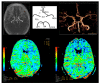

Carotid endarterectomy (CEA) is safe and effective in reducing the risk of stroke in symptomatic severe carotid artery stenosis. Having information about cross-clamping (CC) intolerance before surgery may reduce the complication rate. The purpose of this study was to assess the usefulness of magnetic resonance angiography (MRA) and magnetic resonance angiography perfusion (P-MR) in determining the risk of CC intolerance during CEA.

Material and methods: 40 patients after CEA with CC intolerance were included in Group I, and 15 with CC tolerance in Group II. All patients underwent MRA of the circle of Willis (CoW), P-MR with or without Acetazolamide; P(A)-MR in the postoperative period.

Results: CoW was normal in the MRA in three cases (7.5%) in Group I, and in eight (53%) in Group II. We found P-MR abnormalities in all patients from Group I and in 40% from Group II. Using a calculated cut-off point of 0.322, the patients were classified as CC tolerant with 100% sensitivity or as CC intolerant with 95% specificity. After evaluating P-MR or MRA alone, the percentage of false negative results significantly increased.

Conclusion: The highest value in predicting cross-clamping intolerance is achieved by using analysis of P(A)-MR and MRA of the CoW in combination.